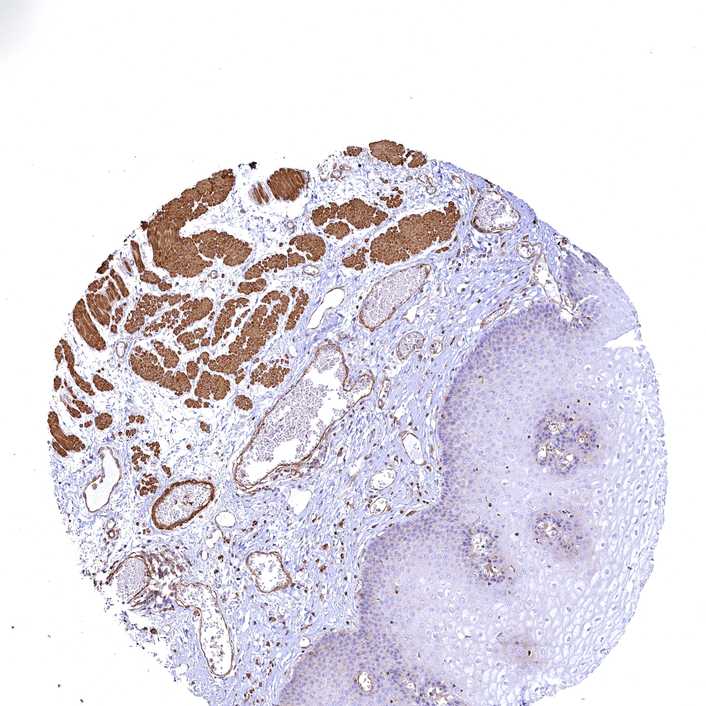

ESOPHAGUS - Antibody stainingi

Antibody staining in the annotated cell types in the current human tissue is reported as not detected, low, medium, or high, based on conventional immunohistochemistry profiling in selected tissues. This score is based on the combination of the staining intensity and fraction of stained cells.

Each image is clickable and will lead to virtual microscopy that enables deeper exploration of all samples and also displays staining intensity scores, fraction scores and subcellular localization as well as patient and tissue information for each sample.

Antibody CAB033678

Squamous epithelial cells Low